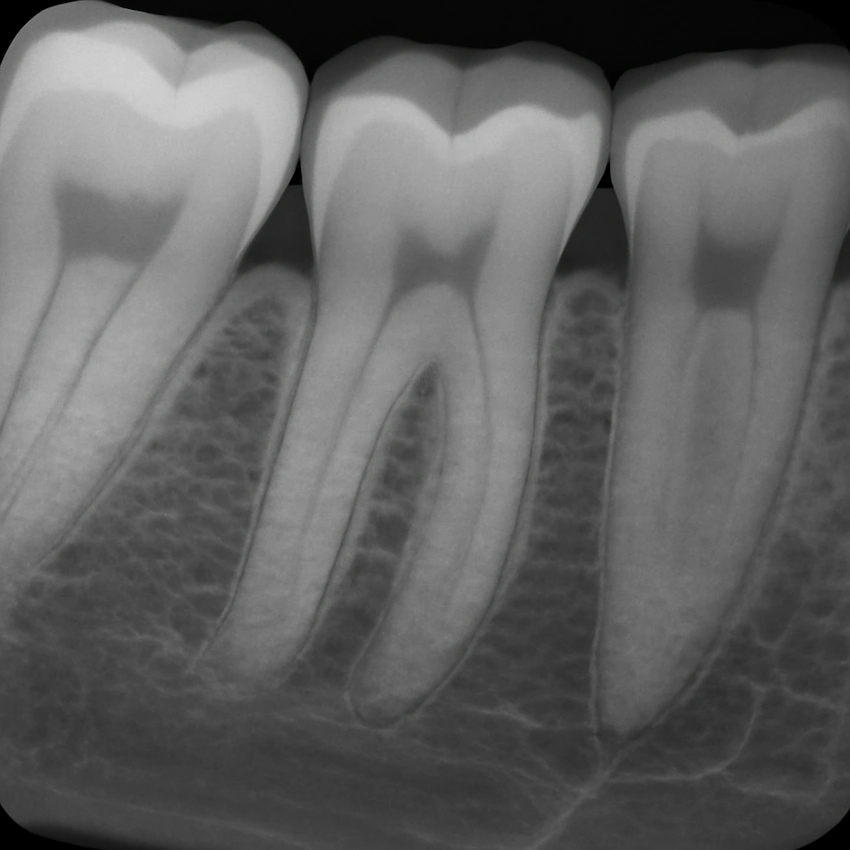

Después de que se realiza una radiografía dental periapical, se asigna el código dental D0389. Una radiografía periapical es una técnica avanzada de imagen donde el enfoque está en las raíces y los huesos alrededor de los dientes. Esta herramienta de vanguardia, favorita de la dentista Polen Akkılıç y su equipo, es un recurso fundamental para solucionar infecciones en la raíz que podrían ser invisibles a simple vista. Además, la radiografía periapical puede ser muy efectiva en condiciones médicas que impliquen infecciones, fracturas, quistes o acumulaciones de pus en la región de la raíz o en los tejidos adyacentes. Este método es solo una de las muchas formas en que la Clínica Dental Lema en Estambul, Turquía, opera para facilitar el diagnóstico y la planificación del tratamiento con alta precisión.

Usando la radiografía periapical, la dentista Polen Akkılıç u otro profesional dental en la Clínica Dental Lema busca obtener la imagen más clara posible no solo del sistema radicular del diente afectado, sino también del hueso que lo rodea y de los ligamentos periodontales. Las visualizaciones ultra detalladas que obtienen son imprescindibles para detectar infecciones en la raíz que podrían causar problemas aún mayores si no se tratan, como extenderse más allá del hueso, lo que en última instancia permite diseñar regímenes de tratamiento efectivos que mejoran la salud bucal general del paciente.

Una de las principales intervenciones dentales es la radiografía periapical, que se centra en las raíces y los huesos y se realiza mediante el método D0389. Las imágenes detalladas son muy útiles para descubrir problemas dentales ocultos que no son visibles a simple vista durante un examen clínico normal, como infecciones, fracturas o abscesos. Este proceso generalmente se realiza en las clínicas dentales locales, incluyendo Lema Dental Clinic.

Imagen radiográfica periapical: El componente principal del procedimiento D0389 es la obtención de una radiografía periapical con gran detalle, que muestra la raíz del diente y el hueso que lo rodea.

Imágenes focalizadas de áreas específicas: Este procedimiento se centra principalmente en la zona de la raíz del diente, capturando las imágenes más detalladas que muestran el estado exacto de la raíz, como infecciones, abscesos, fracturas o quistes.